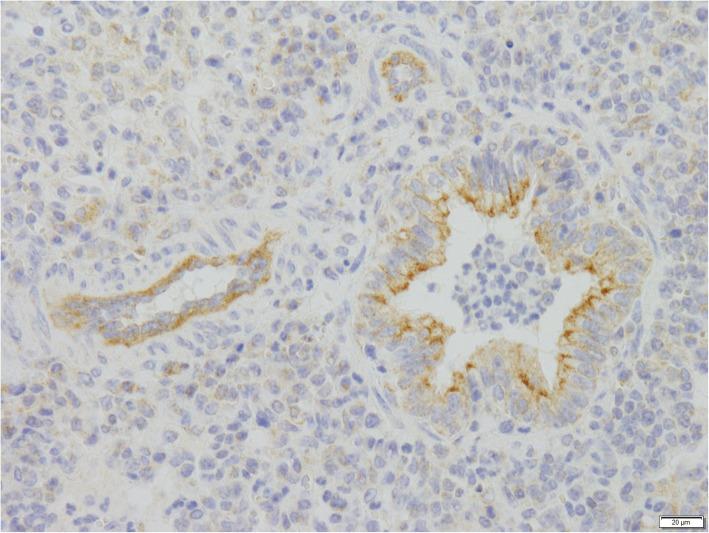

Bovine Respiratory Syncytial virus (BRSV) and Bovine Parainfluenza 3 virus (BPIV3) are closely related viruses involved in and both important pathogens within bovine respiratory disease (BRD), a major cause of morbidity with economic losses in cattle populations around the world. The two viruses share characteristics such as morphology and replication strategy with each other and with their counterparts in humans, HRSV and HPIV3. Therefore, BRSV and BPIV3 infections in cattle are considered useful animal models for HRSV and HPIV3 infections in humans.The interaction between the viruses and the different branches of the host's immune system is rather complex. Neutralizing antibodies seem to be a correlate of protection against severe disease, and cell-mediated immunity is thought to be essential for virus clearance following acute infection. On the other hand, the host's immune response considerably contributes to the tissue damage in the upper respiratory tract.BRSV and BPIV3 also have similar pathobiological and epidemiological features. Therefore, combination vaccines against both viruses are very common and a variety of traditional live attenuated and inactivated BRSV and BPIV3 vaccines are commercially available.

牛呼吸道合胞体病毒(BRSV)和牛副流感病毒 3 型(BPIV3)是密切相关的病毒,都与牛呼吸道疾病(BRD)有关,BRD 是全球牛群发病率和经济损失的主要原因。这两种病毒与人类中的相应病毒 HRSV 和 HPIV3 具有相似的形态和复制策略等特征。因此,牛的 BRSV 和 BPIV3 感染被认为是人类的 HRSV 和 HPIV3 感染的有用动物模型。病毒与宿主免疫系统的不同分支之间的相互作用相当复杂。中和抗体似乎是预防严重疾病的相关因素,细胞介导的免疫被认为是急性感染后清除病毒所必需的。另一方面,宿主的免疫反应对呼吸道上部的组织损伤有很大的贡献。BRSV 和 BPIV3 也具有相似的病理生物学和流行病学特征。因此,针对这两种病毒的联合疫苗非常常见,各种传统的活减毒和灭活 BRSV 和 BPIV3 疫苗都有市售。